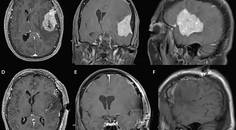

Challenge Case Report: A Woman With a Large Dural-Based Lesion

Javed Khader Eliyas, MD; Rimas V. Lukas, MDJaved Khader Eliyas, MD; Rimas V. Lukas, MD - Imaging & Testing